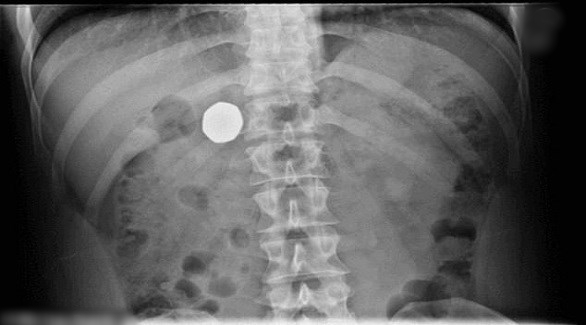

وقال الأطباء، وفق ما ذكرت شبكة “24” الإماراتية، إن الفحوصات والصور الشعاعية أظهرت أن القطعة النقدية لا تزال موجودة في جوف الرجل، وأنهم نصحوه بأن يتابع حياته بشكل طبيعي حتى تخرج القطعة النقدية مع البراز.